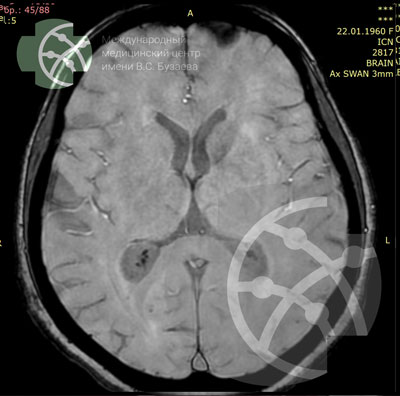

SWAN** axial / 3 мм

** SWAN – diagnosis of brain hemorrhages, helps identify fresh hemorrhages and traces of old hemorrhages – calcifications